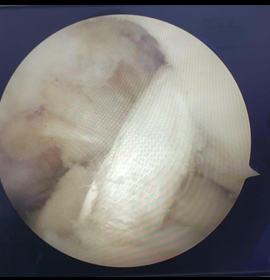

La artroscopia es una técnica quirúrgica de mínima invasión, la cual consiste en la introducción, de una camara (artroscopio) en una articulación mediante una pequeña incisión en la cual nos permite realizar una evaluación completa, un diagnóstico y al mismo tiempo realizar un tratamiento en las articulaciones. ofreciendo mejores resultados, como por ejemplo en lesiones de manguito rotador, lesiones meniscales o ligamentarias de rodilla u otras articulaciones como tobillo, brindando mayor rapidez de recuperación y reduciendo las probabilidades de complicaciones en comparación con las técnicas abiertas.